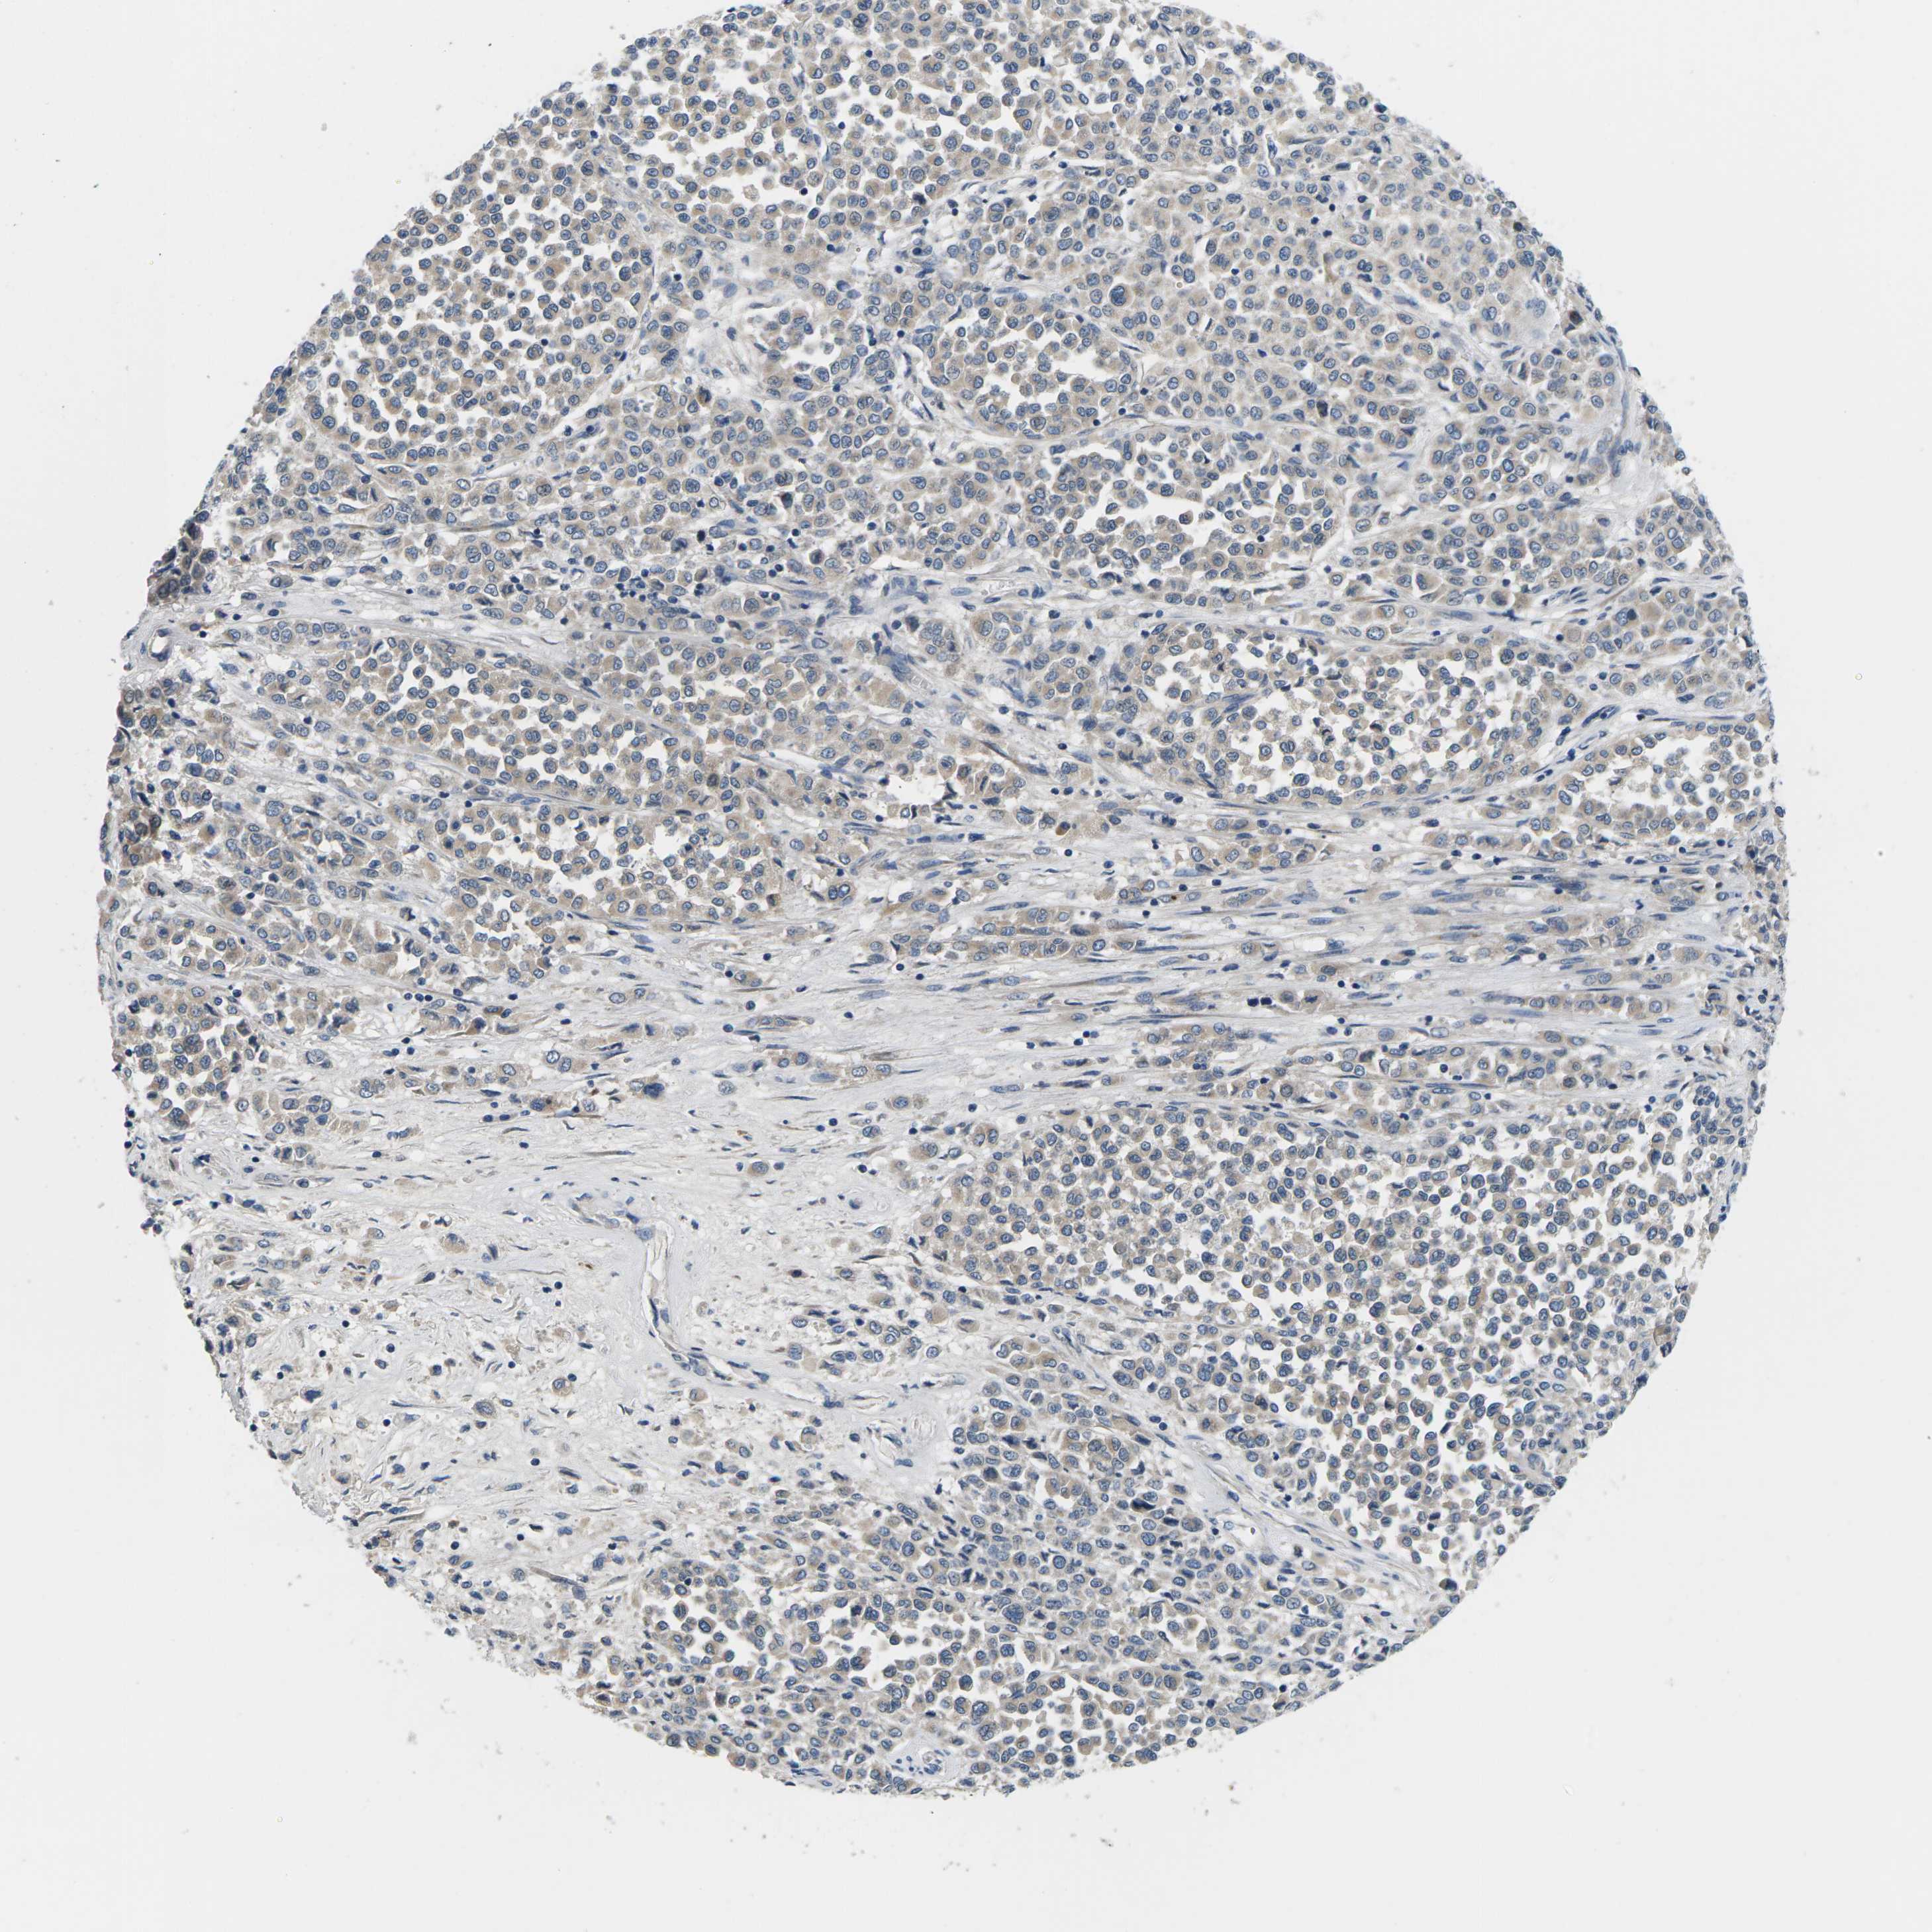

MELANOMA - Protein expressioni

A mouse-over function shows sample information and annotation data. Click on an image to view it in a full screen mode. Samples can be filtered based on level of antibody staining by selecting one or several of the following categories: high, medium, low and not detected. The assay and annotation is described here.

Note that samples used for immunohistochemistry by the Human Protein Atlas do not correspond to samples in the TCGA dataset.

Antibody stainingi

Antibody staining in the annotated cell types in the current human tissue is reported as not detected, low, medium, or high, based on conventional immunohistochemistry profiling in selected tissues. This score is based on the combination of the staining intensity and fraction of stained cells.

Each image is clickable and will lead to virtual microscopy that enables deeper exploration of all samples and also displays staining intensity scores, fraction scores and subcellular localization as well as patient and tissue information for each sample.

Antibody HPA015242

Antibody HPA015968

Malignant melanoma, NOS

Malignant melanoma, Metastatic site